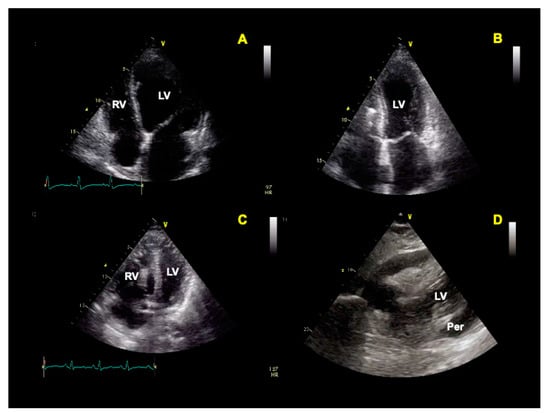

- Carrizales-Sepúlveda, E.F.; Vera-Pineda, R.; Flores-Ramírez, R.; Hernández-Guajardo, D.A.; Pérez-Contreras, E.; Lozano-Ibarra, M.M.; Ordaz-Farías, A. Echocardiographic Manifestations in COVID-19: A Review. Heart Lung Circ. 2021, 30, 1117–1129. [Google Scholar] [CrossRef]

- Cau, R.; Bassareo, P.; Saba, L. Cardiac Involvement in COVID-19—Assessment with Echocardiography and Cardiac Magnetic Resonance Imaging. SN Compr. Clin. Med. 2020, 2, 845–851. [Google Scholar] [CrossRef] [PubMed]

- Citro, R.; Pontone, G.; Bellino, M.; Silverio, A.; Iuliano, G.; Baggiano, A.; Manka, R.; Iesu, S.; Vecchione, C.; Asch, F.M.; et al. Role of multimodality imaging in evaluation of cardiovascular involvement in COVID-19. Trends Cardiovasc. Med. 2020, 31, 8–16. [Google Scholar] [CrossRef] [PubMed]

| Pericardial involvement with effusion |